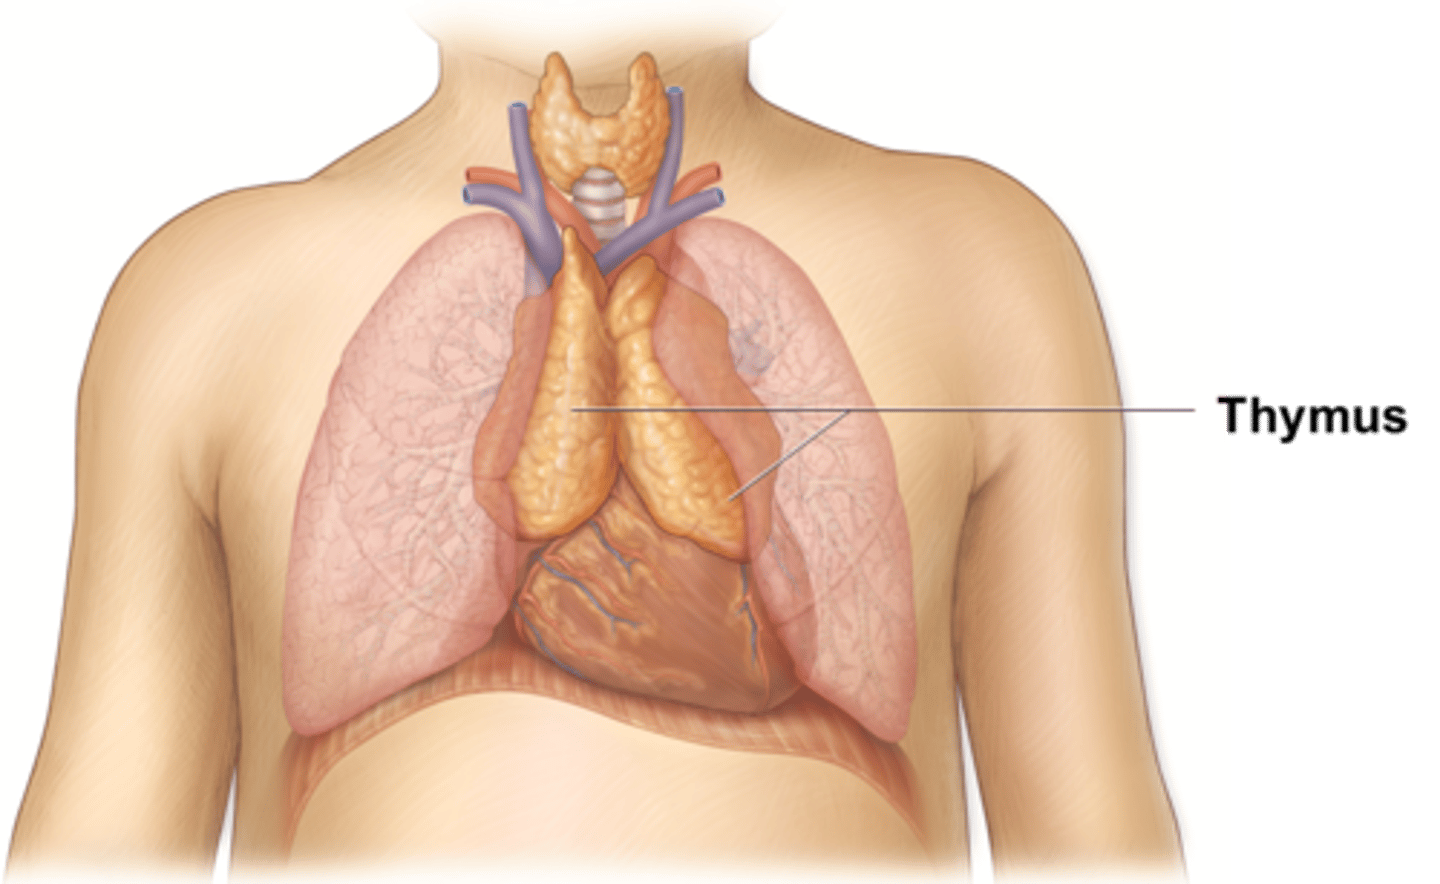

thymus

An immune organ located near the heart. The site of T cell maturation and is larger in children and adolescents.